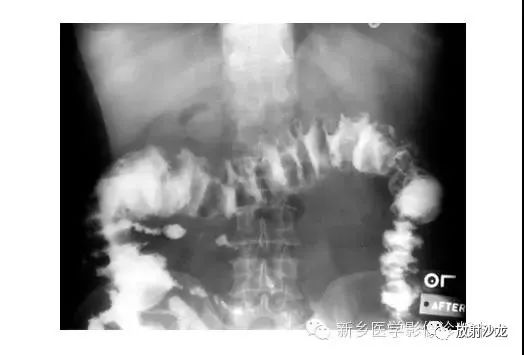

这例腹痛患者的主要异常在哪里?

该X光片显示伪膜性肠炎患者结肠袋广泛增厚(箭头)。结肠袋是结肠上小的囊袋状突起,这种分段的外观可以有助于在X线平片上区分小肠与结肠。伪膜性肠炎中,增厚的肠壁是由肠壁水肿引起的。典型的表现是结肠扩张、呈结节状增厚的结肠袋和拇指印。此X线片横结肠明显增厚。

钡剂灌肠进一步突出结肠袋增厚。